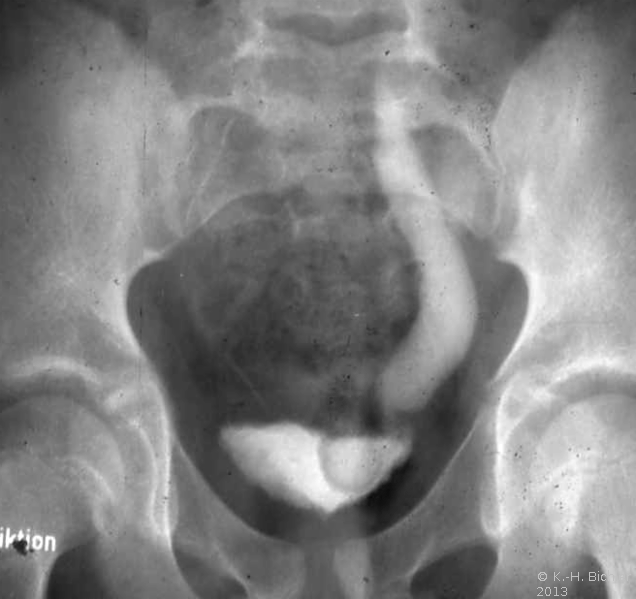

Bei dem 16 Jahre alten Jungen wurde aufgrund der ausgedehnten Ureterozele mit sekundärem partiellem Megaureter insbesondere Dilatation des Harnleiters und länger dauernden rezidivierenden Harnwegsinfekten eine offen Ureterozelenabtragung und Ureterreimplantation durchgeführt (Abbildung 7).